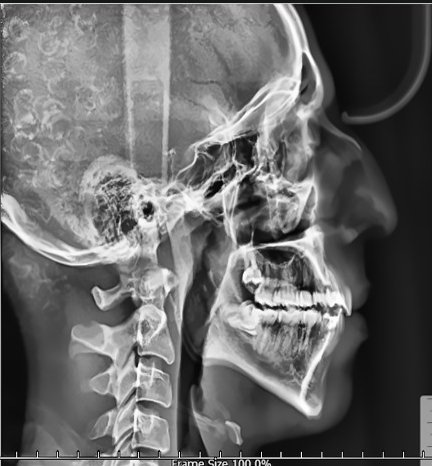

The outcomes of the pre-processing techniques are illustrated in Fig. 4. The combined use of CLAHE and NLM effectively enhances the contrast of soft-tissue regions and improves the visibility of skeletal structures. As shown, the processed images display sharper boundaries and clearer anatomical details, which facilitate more accurate landmark localization in subsequent stages.

Refer to caption

(a)

(b)

Fig. 4: Example cephalogram (a) before and (b) after applying the preprocessing pipeline described in Section 2.2. The enhanced image (b) exhibits improved soft-tissue contrast and clearer bone contours.